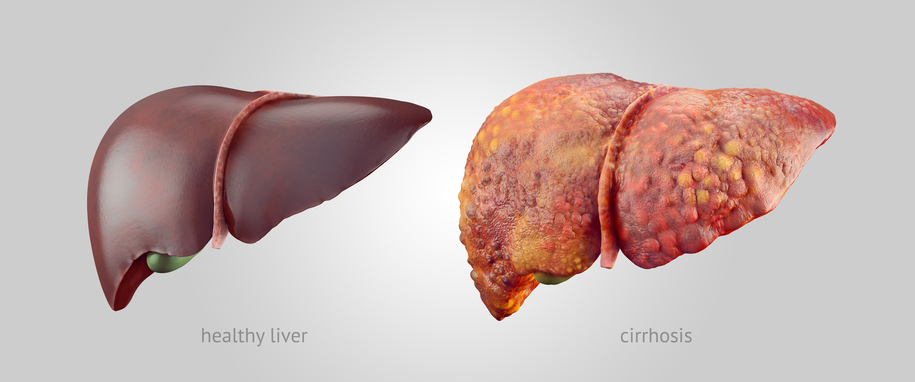

Alcoholism is an ever growing problem faced by societies throughout the world. About 86 percent of Americans over the age of 18 reported drinking at some point in their lifetime. Alcohol Awareness Month, held on April of every year, aims at increasing awareness about its causes, treatment, and recovery. This year the theme is “Changing ...click here to read more